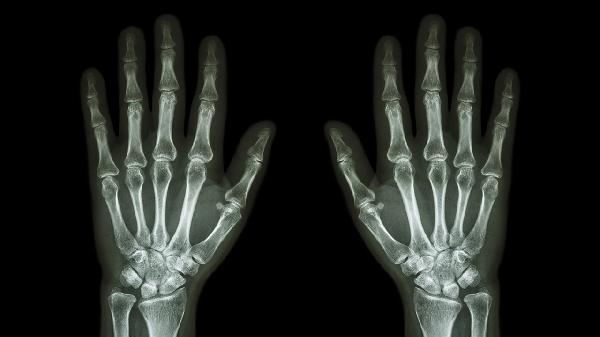

手指关节疼痛肿胀可遵医嘱使用布洛芬缓释胶囊、双氯芬酸钠缓释片、塞来昔布胶囊、硫酸氨基葡萄糖胶囊、甲氨蝶呤片等药物。手指关节疼痛肿胀可能与外伤、骨关节炎、类风湿关节炎、痛风性关节炎、感染性关节炎等因素有关,建议及时就医明确病因。